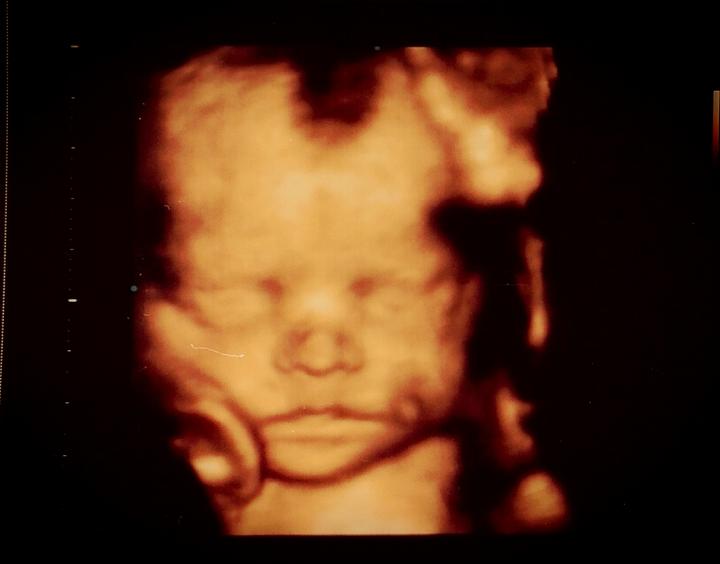

Zdravím Vás dámy 🙂 tak dnes kontrola 20+1tt a už nám potvrdili že budeme 100% chlapák 🙂 fotečku bohužel nemám, mám video ale to netušim jak se sem dává 🙂 vše je v pořádku a rosteme jako z vody... délka od hlavičky k zadečku 15cm a váha 400g... už ted se těšim až náš poklad zase uvidim 🙂